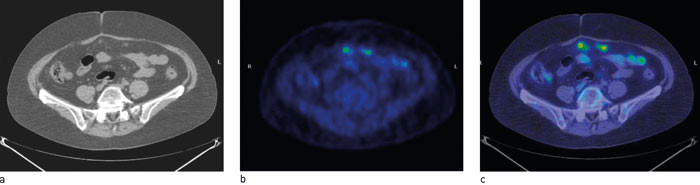

11C-hydroksytryptofan (11C-5-HPT) er et radiofarmakon utviklet ved Universitetet i Uppsala. 11C-5-HTP akkumuleres spesifikt i svulster som produserer eller kan produsere serotonin (13) – (17). 11C-5-HTP-PET viser derfor høyt opptak i en rekke forskjellige nevroendokrine svulster som f.eks. de karsinoide (fig 1), øycellepancreastumorer, men også ikke-funksjonelle endokrine pancreastumorer (13). 11C-5-HPT-PET er bedre enn CT, somatostatinreseptorscintigrafi og er også rapportert bedre enn 18F-DOPA-PET for nevroendokrine svulster i pancreas. Spesielt kan relativt små lesjoner påvises (14, 15). Undersøkelsen er mest relevant for å kartlegge usikre lesjoner ved planlagt kurativ metastasekirurgi og ved utredning av suspekt klinisk residiv som ikke lar seg påvise med CT og scintigrafi. Ytterligere indikasjon for 11C-5-HPT-PET er oppfølging av behandling når resultatene av radiologiske, biokjemiske og kliniske undersøkelser divergerer.